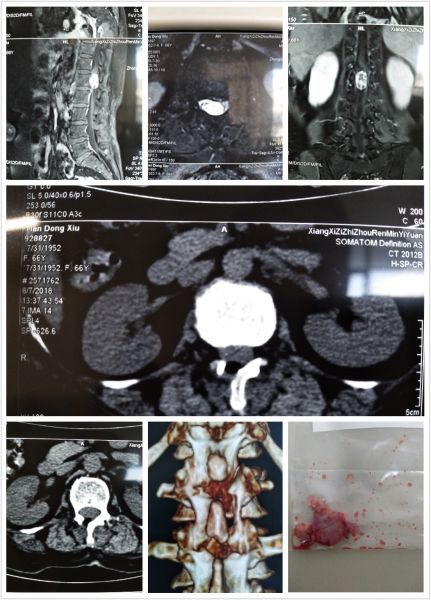

近日,神经外科一病区精准定位,成功完成经半椎板切除免固定治疗椎管内神经鞘瘤一例。

患者田某半年前无明显诱因出现双下肢疼痛,呈放射状,以大腿外侧明显,疼痛剧烈,难以行走,伴肢体麻木,症状反复发作。在我院疼痛科住院治疗,诊断为“椎管内占位,考虑神经鞘瘤可能性大”,疼痛科请神经外科会诊,建议转神经外科手术治疗。

神经外科一病区向昌华主任组织万一副主任、毛辉医师为主的医疗团队,经过完善的术前讨论,精密的术前定位,在全麻下经半椎板切除行椎管内肿瘤切除术,术中肿瘤完整切除,无明显神经功能缺失,脊柱稳定性无明显受损,疼痛症状基本缓解,患者恢复顺利。

随着显微技术的发展,神经外科在治疗脊柱肿瘤同时,最大程度避免脊柱稳定性破坏,手术无需切除棘突和脊间韧带,无需内固定,避免后续固定并发症及高昂的医疗费用。